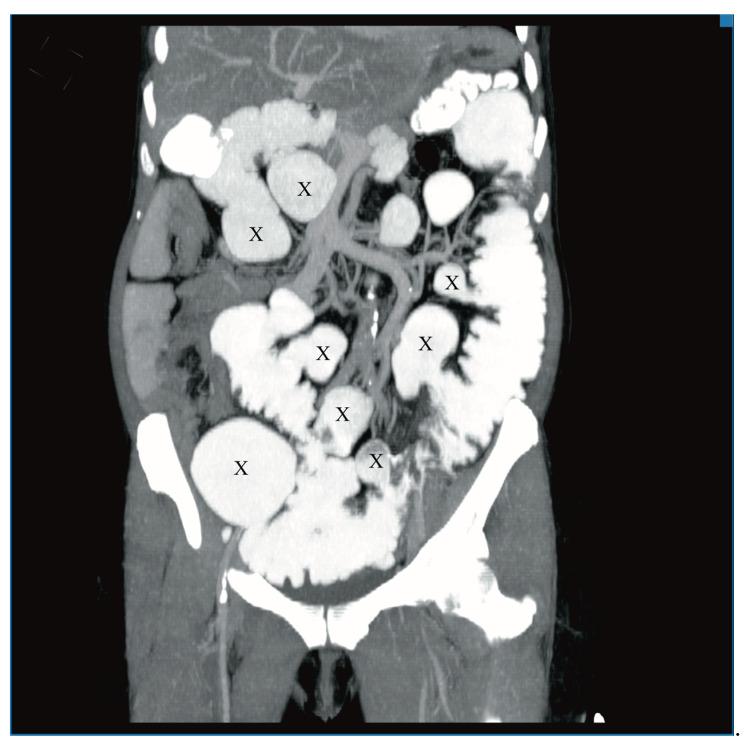

空肠憩室病和空肠脂肪瘤病是罕见病症。通常无症状,但在某些情况下可能引发严重并发症。肠套叠在成年人中并不常见,但如果能迅速诊断,可通过手术治疗,通常预后良好。

我们报告一例60岁女性患者,有慢性营养不良和贫血病史,主诉急性腹痛、呕吐和腹泻。腹部增强计算机断层扫描(CT)显示肠套叠、多个巨大空肠憩室和多个脂肪瘤。患者接受了紧急手术,但由于病情严重程度无法进行根治性治疗。一个月后,因脂肪瘤导致回肠造口梗阻,需要再次手术。患者因营养不良和并发的代谢紊乱病情恶化,最终死亡。